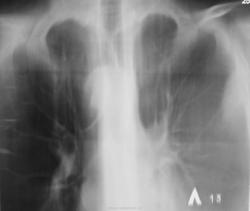

Зацепили по "флюшке"...

Было высказано продположение о наличии специфического процесса. Была рекомендована консультация фтизиатра. Однако, обстоятельства распорядились в другом векторе. Пациент был госпитализирован в хирургическое отделение был пунктирован, проведено противовоспалительное лечение... и через две недели был назначен рентген-контроль.

После проведенного исследования вновь, повторно была рекомендована консультация фтизиатра. Однако, фтизиатры патологию своей не признали.

Прошел год, пациент значительно потерял в весе, температура около 38 градусов, кашель с мокротой и был доставлен в рентгеновский кабинет на носилках.

"Ой"! Воскликнули фтизиатры, это наше! На носилках пациент был срочно госпитализирован в областную туб больницу в тяжелом состоянии. Лечение, со слов фтизиатров, было не легким, так сказать - "на грани", пациент был прооперирован.